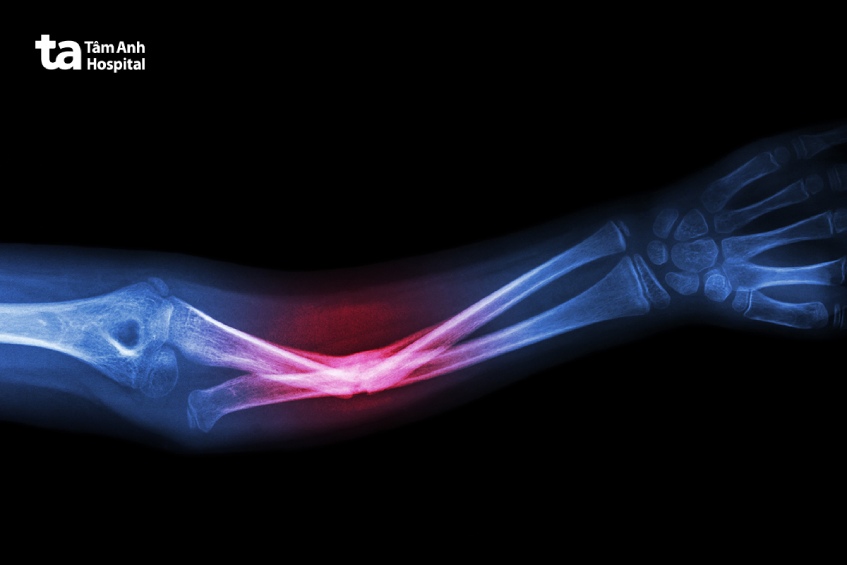

Chụp X-quang tay là một kỹ thuật chẩn đoán hình ảnh sử dụng tia bức xạ X để tạo ra hình ảnh bên trong bàn tay, cẳng tay, cánh tay của người bệnh. Hình ảnh X-quang thu được sẽ cho thấy cấu trúc bên trong (giải phẫu) xương toàn bộ cánh tay của người bệnh với màu đen và trắng. Canxi trong xương sẽ hấp thụ nhiều bức xạ hơn, vì vậy trên hình ảnh chụp X-quang phần xương sẽ hiển thị màu trắng.

Các mô mềm như cơ, mỡ và các cơ quan sẽ hấp thụ ít bức xạ hơn, vì vậy trên hình ảnh X-quang sẽ hiển thị nhiều màu xám khác nhau. Hình ảnh X quang sẽ giúp bác sĩ có thể chẩn đoán các tổn thương ở bộ phận chi trên, từ đó đưa ra hướng điều trị phù hợp nhất cho người bệnh.